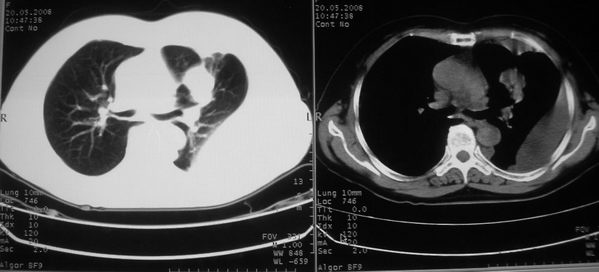

以下是引用w_jianhua在2008-5-22 12:59:00的发言:[br]1.左肺上叶肺癌并左侧胸腔积液可能性大。2不除外支气管内膜结核并包裹性胸腔积液,建议支气管镜检3.左肺下叶肺大泡,肺气肿